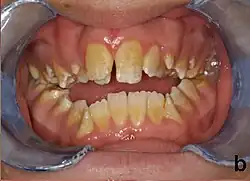

People with amelogenesis imperfecta may have teeth with abnormal color: yellow, brown or grey; this disorder can affect any number of teeth of both dentitions. Enamel hypoplasia manifests in a variety of ways depending on the type of AI an individual has (see below), with pitting and plane-form defects common.[4] The teeth have a higher risk for dental cavities and are hypersensitive to temperature changes as well as rapid attrition, excessive calculus deposition, and gingival hyperplasia.[5] The earliest known case of AI is in an extinct hominid species called Paranthropus robustus, with over a third of individuals displaying this condition.[6]

AI can be classified according to their clinical appearances:[19]

- Type 1 - Hypoplastic

- Enamel of abnormal thickness due to malfunction in enamel matrix formation. Enamel is very thin but hard & translucent, and may have random pits & grooves. Condition is of autosomal dominant, autosomal recessive, or x-linked pattern. Enamel differs in appearance from dentine radiographically as normal functional enamel.[20]

- Type 2 - Hypomaturation

- Enamel has sound thickness, with a pitted appearance. It is less hard compared to normal enamel, and are prone to rapid wear, although not as intense as Type 3 AI. Condition is of autosomal dominant, autosomal recessive, or x-linked pattern. Enamel appears to be comparable to dentine in its radiodensity on radiographs.

- Type 3 - Hypocalcified

- Enamel defect due to malfunction of enamel calcification, therefore enamel is of normal thickness but is extremely brittle, with an opaque/chalky presentation. Teeth are prone to staining and rapid wear, exposing dentine. Condition is of autosomal dominant and autosomal recessive pattern. Enamel appears less radioopaque compared to dentine on radiographs.

- Type 4 - Hypomature hypoplastic enamel with taurodontism

- Enamel has a variation in appearance, with mixed features from Type 1 and Type 2 AI. All Type 4 AI has taurodontism in common. Condition is of autosomal dominant pattern. Other common features may include an anterior open bite,[21] taurodontism, sensitivity of teeth.